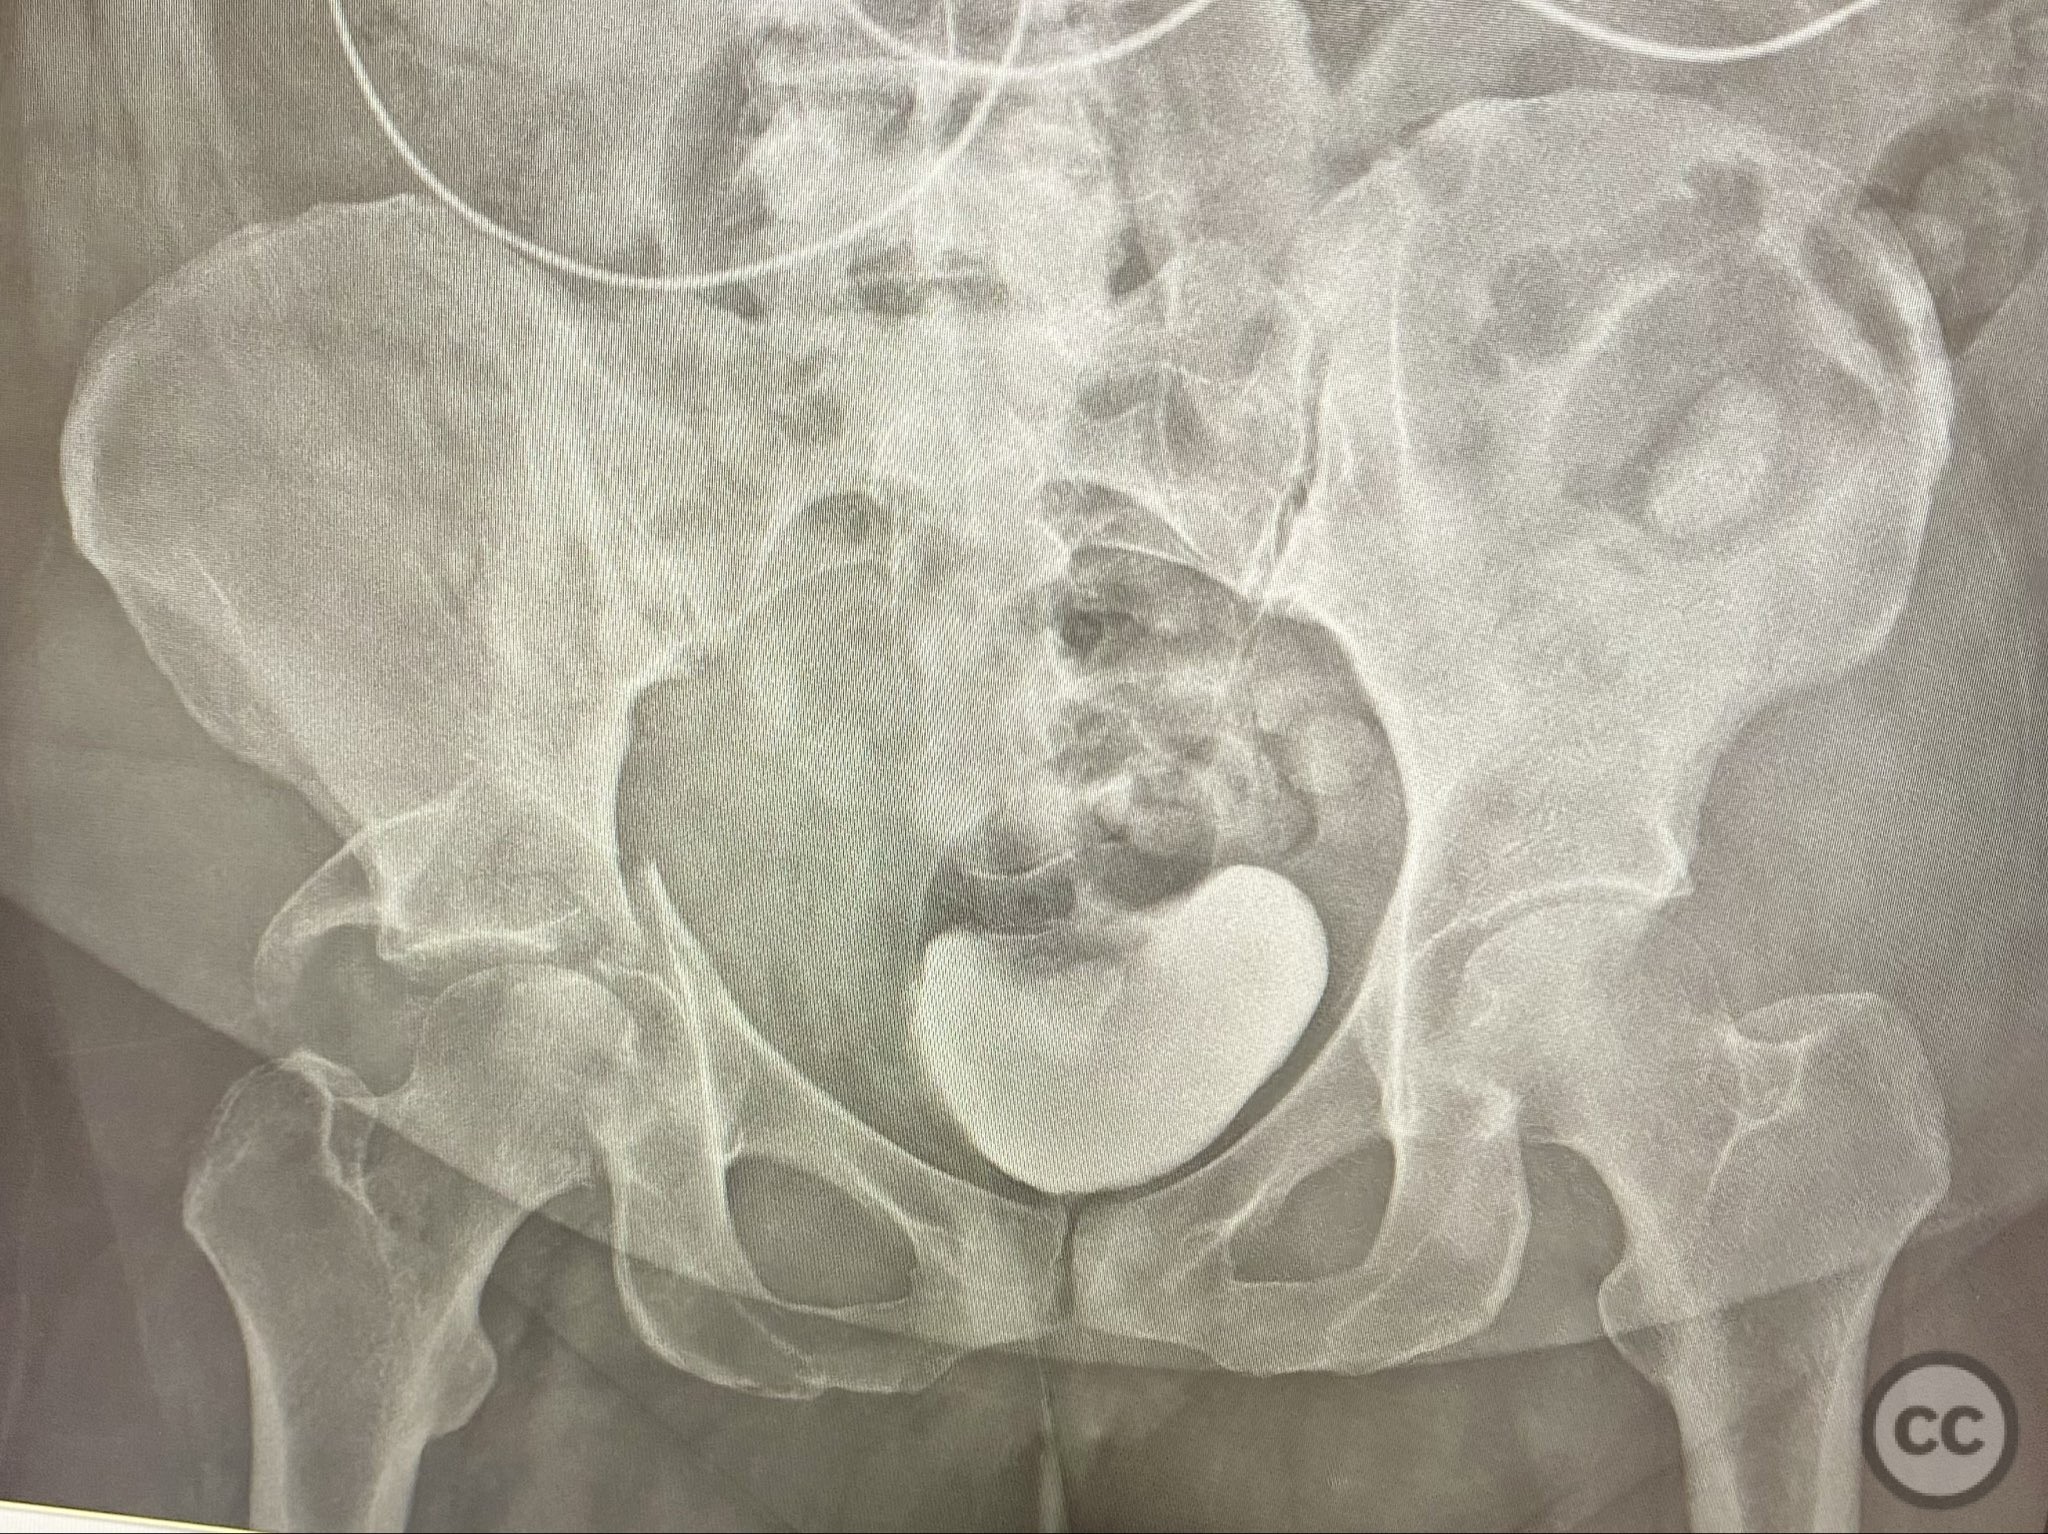

Clinical and radiological findings:  A high-speed motor vehicle collision resulted in a closed transverse acetabular fracture with associated comminuted posterior wall (PW) fracture-dislocation. The femoral head exhibited impaction and comminution, with local cancellous bone crushed and the femoral head itself also sustaining compressive injury from the denser acetabular bone. Neurovascular examination was unremarkable. Initial CT imaging delineated the acetabular fracture planes, displacement, comminution of the posterior wall, femoral head impaction, and absence of soft tissue attachment to the caudal PW fragment.

The transverse fracture was manipulated and temporarily stabilized using a reduction clamp applied across the fracture plane. Under biplanar fluoroscopic guidance, a cannulated cancellous lag screw was percutaneously inserted to achieve interfragmentary compression across the transverse component. The reduction clamp was then removed. Posterior wall fragments were anatomically reduced and stabilized with contoured buttress plates spanning both the posterior wall and providing additional stabilization to the transverse component. Postoperative CT confirmed satisfactory reduction and fixation of both acetabular columns and restoration of articular congruity.

Postoperative protocol:   Postoperatively, skeletal traction was discontinued. The patient was maintained non-weight bearing on the affected limb for 8 weeks, with early passive range of motion exercises initiated at 48 hours post-surgery. Progressive weight bearing was introduced after radiographic evidence of healing at 8–10 weeks.